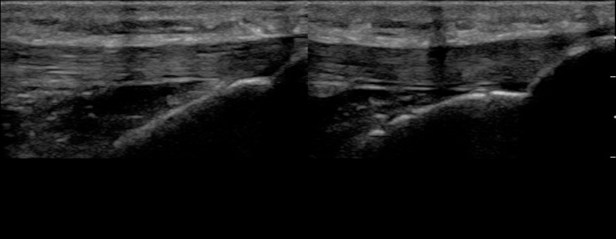

Figure 3. Demonstration of normal muscle on ultrasound in a short axis plane. It appears hypoechoic to fascia, epidermis, and bone. Within the muscle there are small hyperechoic portions that are layering of striated muscle, fascia, or neurovascular bundles.